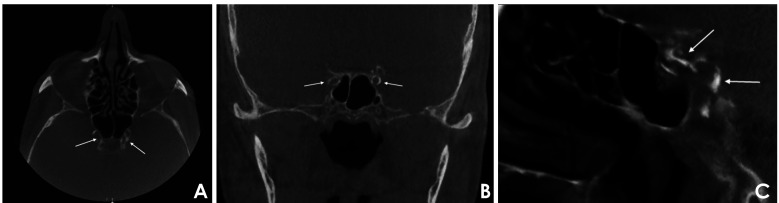

目的:本研究旨在评估偶发性血管钙化样影像学表现与自我报告的医疗数据之间的相关性,并评估报告的诱发因素与使用锥形束计算机断层扫描(CBCT)数据的影像学表现之间的关系。材料和方法:对188名男性和203名女性的391张CBCT扫描进行匿名分析,以确定颅外颈动脉和颅内颈动脉钙化(ECAC和ICAC分别)和Mönckeberg内侧硬化(MMS)的迹象。根据患者自述的病史将其分为4组。描述性统计用于评估数据,随后通过简单的单变量逻辑回归分析进行验证。结果:在391张CBCT扫描中,23.27%显示ECAC, 42.71%显示ICAC, 1.8%显示MMS。结论:这些发现强调了对牙科患者进行全面治疗前病史评估的重要性,特别是当在CBCT成像上观察到血管钙化样征象时。

Results: Among the 391 CBCT scans reviewed, 23.27% exhibited ECAC, 42.71% demonstrated ICAC, and 1.8% showed MMS. Statistical analysis revealed a significant correlation (P<0.05) between both ECAC and ICAC and self-reported predisposing factors-including hypertension, cardiovascular disease, dyslipidemia, diabetes mellitus, and sleep apnea/chronic obstructive pulmonary disease-with notable differences among the study categories (P<0.05). In addition, a strong correlation (P<0.001) was found between the presence of ECAC, ICAC, and MMS and increasing age. Men were significantly more susceptible to ECAC than women (P<0.05).